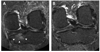

Objectives: To describe the natural history of subchondral bone marrow lesions (BMLs) in a sample of subjects with knee osteoarthritis (OA) or at risk of developing it. Additionally, to examine the association of change in BMLs from baseline to 30-month follow-up with the risk of cartilage loss in the same subregion at follow-up.

Methods: 1.0 T MRI was performed using proton density-weighted, fat-suppressed sequences. BML size and cartilage status were scored in the same subregions according to the WORMS system. Subregions were categorised based on comparison of baseline and follow-up BML status. A logistic regression model was used to assess the association of change in BML status with cartilage loss over 30 months using stable BMLs as the reference group.

Results: 395 knees were included. 66% of prevalent BMLs changed in size; 50% showed either regression or resolution at follow-up. The adjusted odds ratios (95% confidence intervals) of cartilage loss in the same subregion at follow-up for the different groups were 1.2 (0.5 to 1.6) for regressing BMLs, 0.9 (0.5 to 1.6) for resolving BMLs, 2.8 (1.5 to 5.2) for progressing BMLs, 0.2 (0.1 to 0.3) for subregions with no BMLs at baseline and follow-up and 3.5 (2.1 to 5.9) for newly developing BMLs. BML size at baseline was associated with risk of subsequent cartilage loss.

Conclusions: The majority of pre-existing BMLs decreased in size at follow-up. Absence of BMLs was associated with a decreased risk of cartilage loss, while progressing and new BMLs showed a high risk of cartilage loss in the same subregion.